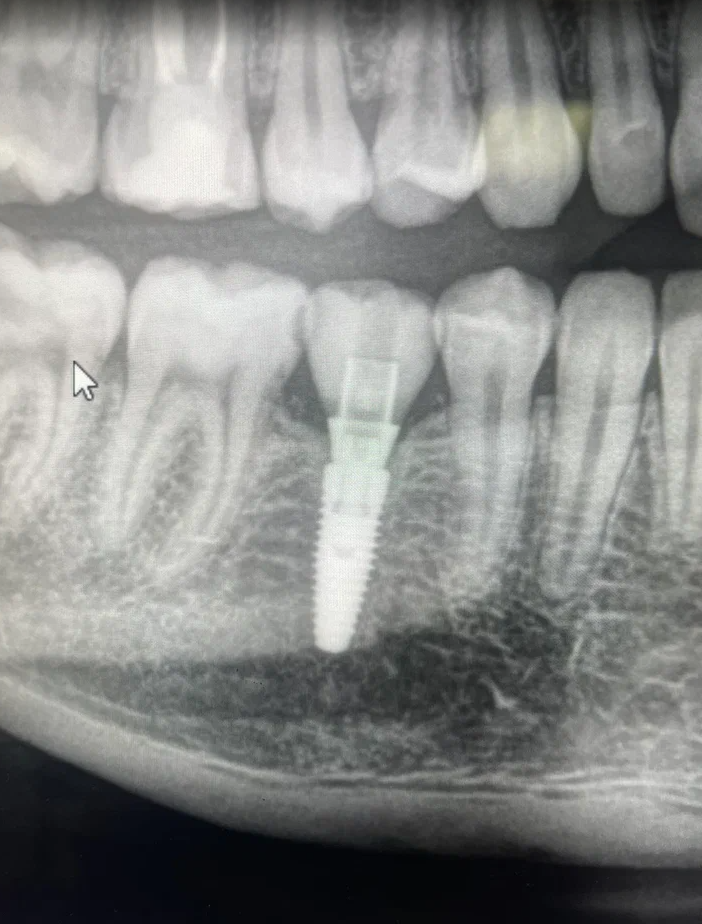

Имплант — это титановый штифт, который хирург устанавливает в кость. После операции начинается процесс заживления и адаптации тканей — он называется остеоинтеграцией.

• Используем цифровое моделирование операции и навигационные шаблоны для точной установки имплантов.